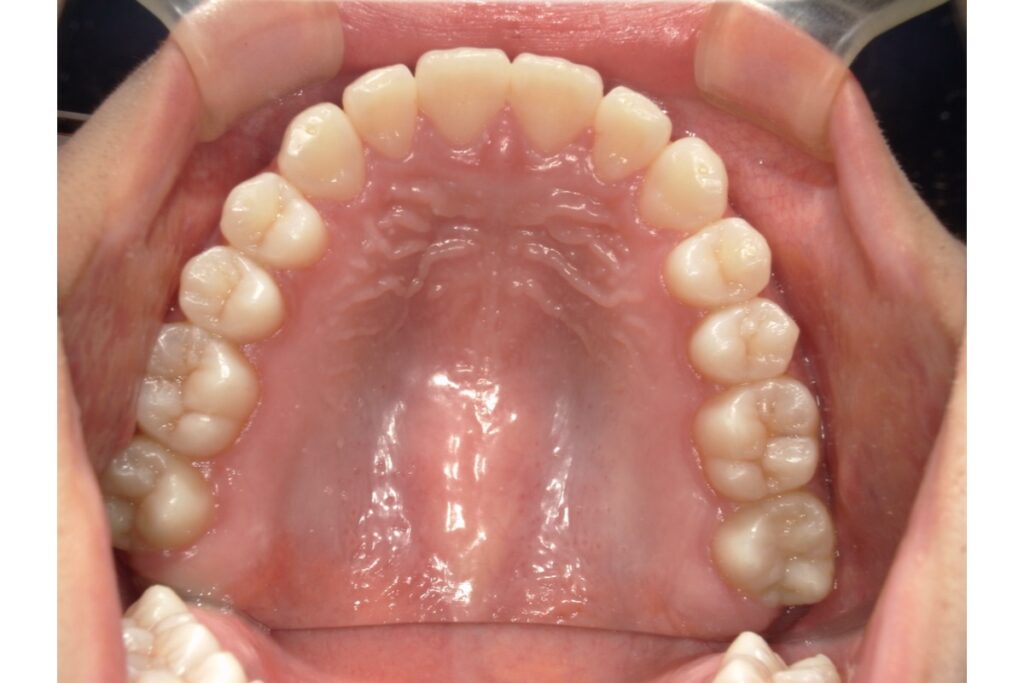

歯列の「アーチ形状」とは?

歯列のアーチとは、上・下の歯が並んでいるカーブの形のことです。

上から見たとき、歯が半円状に並んでいる様子をイメージしてください。

🔸 主な歯列アーチのタイプ

| U字型(広め) | 丸みのある緩やかなカーブ | 歯列が広く、笑顔が明るく見える |

| V字型(狭め) | 尖った形 | 顎が細く見えるが、口元が窮屈な印象に |

| スクエア型 | 前歯が直線的 | 男性的でシャープな印象 |

| 楕円型 | 自然でバランスの良い形 | 多くの人の理想的な歯列形状 |

アーチ形状は、顎の骨の形・歯の大きさ・舌の位置・筋肉の使い方などによって決まります。